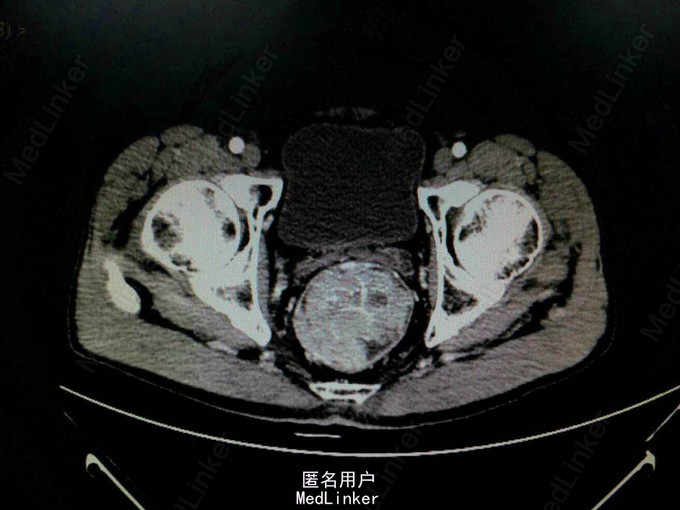

查体:生命体征平稳,心肺未见明显异常,腹平软,无压痛以及反跳痛,未触及明显肿块。直肠指检:胸膝位距肛门5cm可触及1点位有一肠腔生长的肿物,质软,退指指套染血。 辅助检查:全腹+盆腔CT检查提示:直肠肿块,考虑直肠癌可能性大,并直肠系膜内淋巴结转移,请结合肠镜检查。内镜活检提示:1.大肠粘膜呈慢性炎 2.大肠粘膜腺体高级别上皮内瘤变。

诊断:直肠肿物 治疗:拟行腹腔镜下miles术